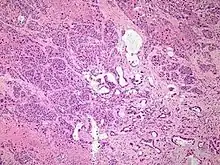

Histopathology

The most common form of pancreatic cancer (adenocarcinoma) is typically characterized by moderately to poorly differentiated glandular structures on microscopic examination. There is typically considerable desmoplasia or formation of a dense fibrous stroma or structural tissue consisting of a range of cell types (including myofibroblasts, macrophages, lymphocytes and mast cells) and deposited material (such as type I collagen and hyaluronic acid). This creates a tumor microenvironment that is short of blood vessels (hypovascular) and so of oxygen (tumor hypoxia).[2] It is thought that this prevents many chemotherapy drugs from reaching the tumor, as one factor making the cancer especially hard to treat.[2][3]

| Cancer type | Relative incidence[11] | Microscopy findings[11] | Micrograph | Immunohistochemistry markers[11] | Genetic alterations[11] |

|---|---|---|---|---|---|

| Pancreatic ductal adenocarcinoma (PDAC) | 90% | Glands and desmoplasia | ![]() | ||

| Pancreatic acinar cell carcinoma (ACC) | 1% to 2% | Granular appearance | ![]() |